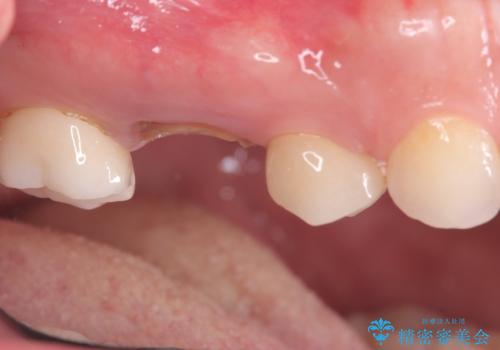

- 治療計画

今回の治療では、まず原因となっていた奥歯を慎重に抜歯し、その直後にインプラントを埋入しました。この抜歯即時埋入により、抜歯からインプラント埋入までの期間を省き、骨の吸収を最小限に抑えられました。治療後は痛みや腫れも少なく、患者様は快適に過ごしていただけました。最終的に、わずか3ヶ月でセラミッククラウンを装着。機能性と審美性を兼ね備えた新しい歯により、長年の痛みが解消され、快適な食生活を取り戻していただけました。